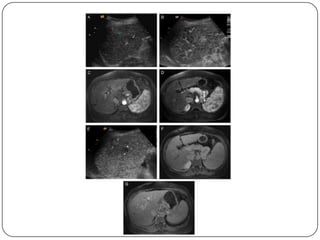

Auxiliares de diagnóstico

 USG

 Imágenes hipoecoicas, encapsuladas y con sombra

acústica, aunque en ocasiones aparecen como

alteraciones inespecíficas de la ecogenicidad, por

lo que resulta difícil diferenciarlas del daño

hepatocelular crónico.

 Sensibilidad (60-80%), Especificidad (45-96%)

 La sensibilidad en el CH alcanza 86%, pero en

lesiones menores de 2 cm es baja.

 Cada 6 meses en pacientes hepatópatas

 RM

 No utiliza contraste intravenoso

 Es más eficaz que la TC para diferenciar el CH de

nódulos de regeneración

 TAC

 Sensibilidad del 68% con especificidad de 93%, se

utiliza para precisar las alteraciones vistas en el

usg.